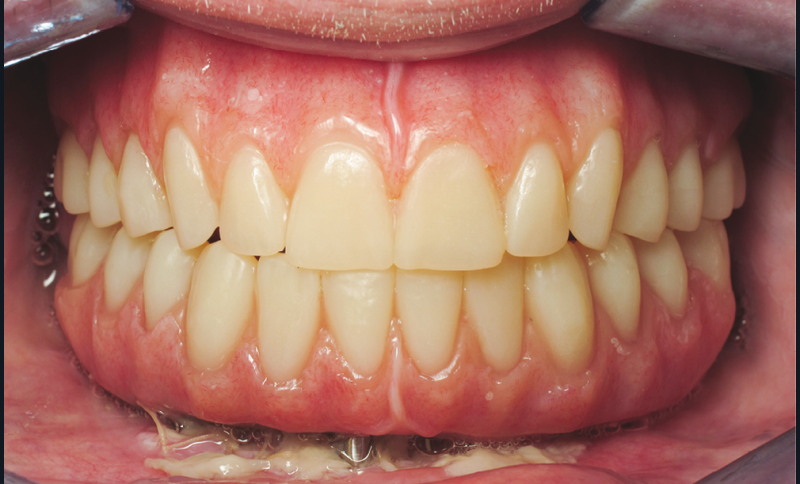

Après démontage et nettoyage du dispositif implantoporté, la barre Trefoil est vissée passivement [7] sur ses analogues grâce à un mécanisme judicieux de rotules compensatrices. Un dernier contrôle de coaptation barre/prothèse est réalisé (fig. 6). L’ensemble est sablé et solidarisé par une résine chémopolymérisable. Après polymérisation, suppression des extensions, aménagement des accès prophylactiques et maquillage composite par addition acté, le bridge d’usage est mis en charge immédiatement (fig. 7).

L’occlusion et les accès prophylactiques sont de nouveau contrôlés. S’ensuivent les séquences de maintenance classiques. Un contrôle radiographique (fig. 8) ainsi qu’une surveillance annuelle sont mis en place.